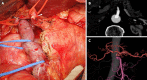

Background: During pancreaticoduodenectomy in patients with celiac axis (CA) stenosis due to compression by the median arcuate ligament (MAL), the MAL has to be divided to maintain hepatic blood flow in many cases. However, MAL division often fails, and success can only be determined intraoperatively. To overcome this problem, we performed endovascular CA stenting preoperatively, and thereafter safely performed pancreaticoduodenectomy. We present this case as a new preoperative treatment strategy that was successful.

Case summary: A 77-year-old man with a diagnosis of pancreatic head cancer presented to our department for surgery. Preoperative assessment revealed CA stenosis caused by MAL. We performed endovascular stenting in the CA preoperatively because we knew that going into the operation without a strategy could lead to ischemic complications. Double-antiplatelet therapy (DAPT) - which is needed when a stent is inserted - was then administered in parallel with neoadjuvant chemotherapy (NAC). This allowed us to administer DAPT for a sufficient period before the main pancreaticoduodenectomy procedure while obtaining therapeutic effects from NAC. Subtotal stomach-preserving pancreaticoduodenectomy was then performed. The operation did not require any unusual techniques and was performed safely. Postoperatively, the patient progressed well, without any ischemic complications. Histopathologically, curative resection was confirmed, and the patient had no recurrence or complications due to ischemia up to six months postoperatively.